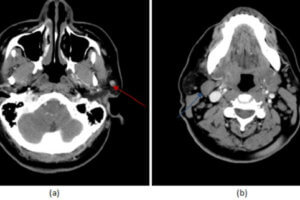

Paraganglioma

Paragangliomas are rare neuroendocrine tumors that originate In the glomus cells of the sympathetic nervous system. The most common location is the carotid space, either involving the carotid body (glomus cells involved... Read more »